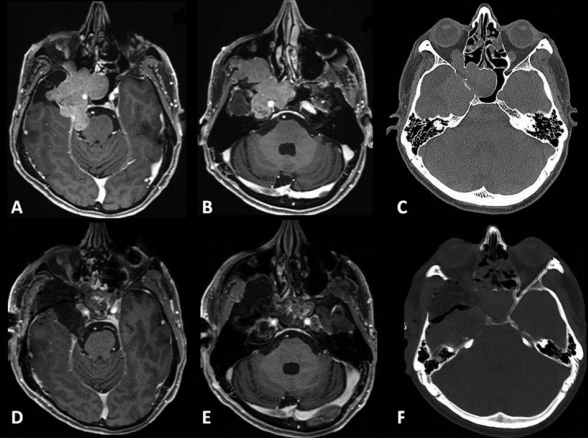

术前和术后图像。(A)术前轴向t1加权钆增强磁共振成像(MRI)显示脑膜瘤延伸至后颅窝(PF)、海绵窦(CS)、眼眶和蝶窦(SS)。(B)肿瘤延伸至中窝、翼腭窝(PPF)和颞下窝(ITF)。(C)术前轴向计算机断层扫描(CT)显示更大的蝶翼侵蚀和SS受累。(D,E)术后轴向t1加权钆增强MRI显示肿瘤完全切除。(F)术后轴位CT扫描显示用于闭合的脂肪移植物。

一名61岁女性出现V1(嗅神经)和V2感觉迟钝和感觉减退。MRI显示增强病灶以右侧海绵窦为中心,延伸至颞窝、SOF、FR、FO、PPF、ITF和SphS(图a-c)。

选择前颞窝入路。对眼眶顶和侧壁、蝶骨大翼和小翼以及前中颅窝底进行钻孔。进行了前床突切除术。将浸润的颞部硬脑膜从海绵窦剥离,并与肿瘤的硬膜内部分一起切除。使用一块颅骨膜封闭硬脑膜。沿着三叉神经部分追踪肿瘤通过FO、FR、SOF和PPF的扩展,并部分切除保留V2和V3。然后,对翼根进行钻孔,确定维迪安管并打开屋顶。SphS通过ALT打开。

还可以通过MS和AMT访问SphS。使用显微镜和内镜通过AMT和ALT将位于SphS的肿瘤完全切除(图6d,e)。使用从颞肌后部获得的肌肉块来封闭SphS的两个开口。术后过程很顺利。除了V2感觉迟钝和感觉减退之外,患者的神经系统保持完好。病理结果为II级脑膜瘤。患者接受了分段放射治疗。

(ITF,颞下窝;PPF,翼腭窝;SphS,蝶窦;ALT,前外侧三角;AMT,前内侧三角;TM,颞肌;V1,眼神经;V2,上颌神经;V3,下颌神经)。